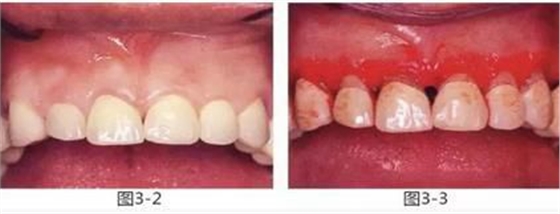

圖3-2 ,3

雖然存在較為淺度的牙周袋和齦下齲壞,但是從齦緣到牙槽嵴頂位置有充足的健全牙體組織和角化齦,因此通過(guò)牙齦切除進(jìn)行了治療。